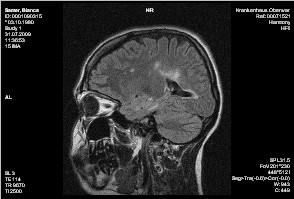

HWS:

Am besten auf der STIR-Sequenz sichtbar finden sich weiträumige T2w Hyperintensitäten im gesamten Myelon, beginnend auf Höhe von C1. Ein Kontrastmittelenhancement ist hierbei nicht erkennbar. Im übrigen geringradige degenerative Wirbelsäulenveränderungen, dargestellt als dorsale Discusvorwölbungen. Hierbei im Segment C3/4 mediolateral bds. am ausgeprägtesten. Insgesamt kein hochgradiger Discusprolaps sowie keine signifikante Wurzelbedrängung.

Ergebnis:

Bekannte Enc. diss.

Im Vergleich mit den mitgebrachten Bildern keine massive Zunahme der

Glialäsionen, keine kontrastmittelaufnehmenden Bezirke als Aktivitätszeichen.